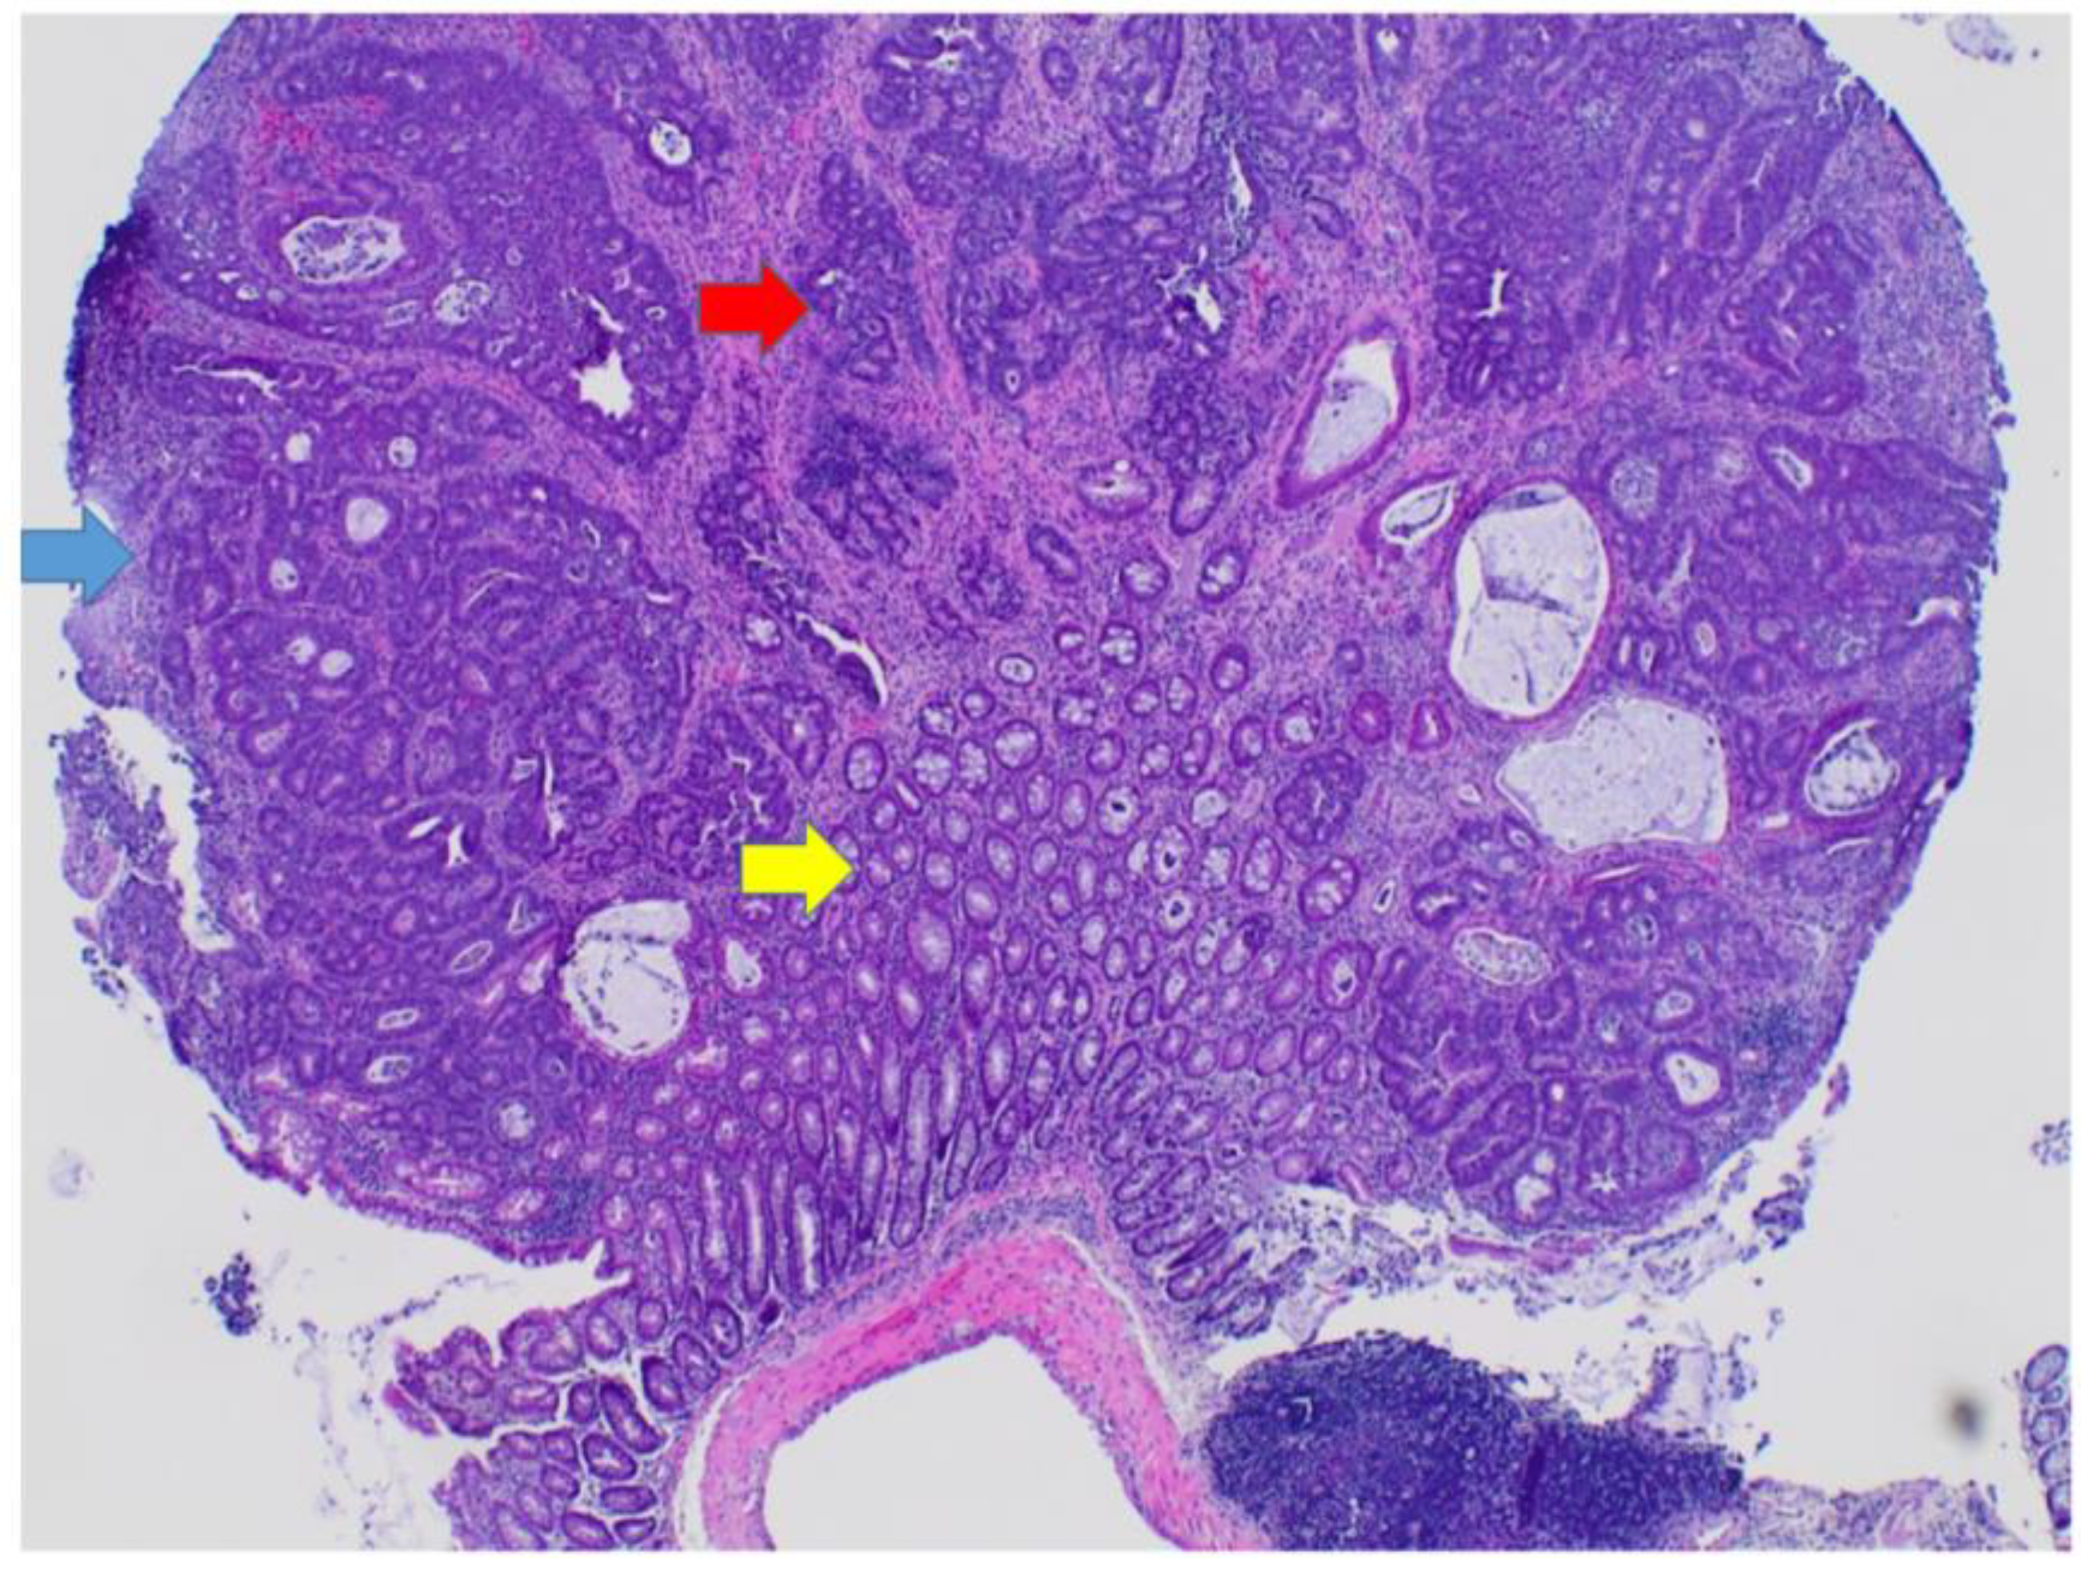

3.5. Polyps Contain Dysplasia and Adenocarcinoma